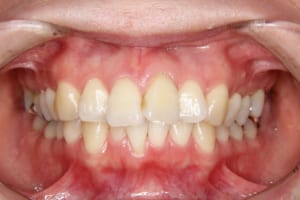

上下顎前突を伴う叢生の医療関係者の方の治療例

治療前

治療後

| 年齢・性別 | 34才 女性 |

|---|---|

| 主訴 | 上の前歯が出ている |

| 治療内容 | リンガルブラケット(舌側矯正/裏側矯正)を使用した成人矯正治療を行いました。 |

| 使用した装置 | リンガルブラケット 歯科矯正用アンカースクリュー(2本) 筋機能訓練(MFT)は行っていません |

| 治療回数 | 33回 |

| 治療期間 | 2年11か月 |

| 抜歯および非抜歯 | 上の左右第一小臼歯、右側第三大臼歯(親知らず) 下の左側第二小臼歯、右側第一小臼歯、左右第三大臼歯(親知らず) |

| 費用(保定除く) | 1,114,020円(税込) |

| リスク・副作用 | 主なものとして、 ・歯の痛み ・虫歯/歯周病 ・口内炎 ・発音障害 ・食事の制限 ・歯肉の退縮(歯茎が下がる) ・知覚過敏 ・歯根吸収(歯の根が短くなる) ・金属やゴムのアレルギーの発症 ・歯髄壊死(歯の神経が死んでしまう) 等のリスクが考えられます。 |

| その他/備考 | 治療上、患者さんのご協力が比較的必要だったケースですが、いつも頑張っていただいてきれいに治療することが出来ました。 いつも笑顔で元気なお母さんという印象でした。スタッフともたくさん色々なお話をしていただきました。 |